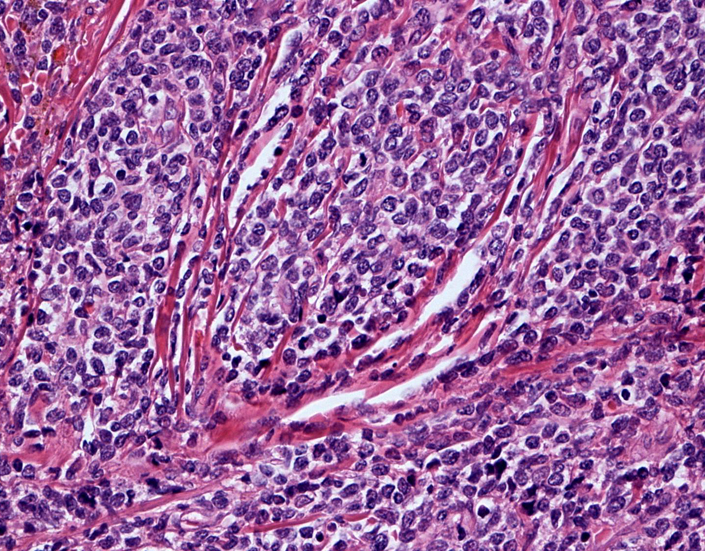

Fig03, Fig04は腫瘍細胞の拡大像。大型異型細胞の出現が認められる。腫瘍細胞はCD4+, CD56+, CD123+

この頃はCD4+, CD56+ にCD123陽性で診断が可能であったが, 他疾患でもこの陽性パターンをとることがわかってきた.